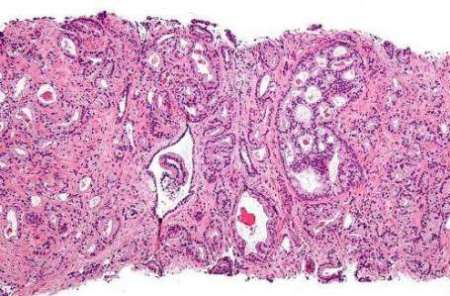

تومورهاي پروستات براي رشد و گسترش به هورمون هاي مردانه به نام آندروژن تكيه دارند و مسدود كردن گيرنده هاي آندروژن مي تواند درمان موثري در اين زمينه باشد.

اين در حالي است كه سلول هاي سرطاني عمدتا مولد اشكال غيرطبيعي از گيرنده آندروژن هستند كه مي توانند در همه زمان ها بدون نياز به تحريك هورمون آندروژن، فعال شوند.